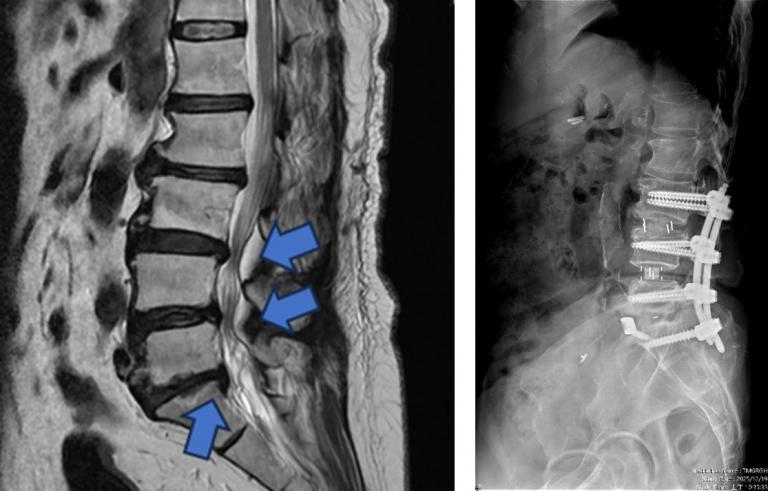

▲【手術前及手術後】手術前有脊椎滑脫不穩定及脊椎狹窄造成神經壓迫(左圖),手術後除了重建椎間高度,也將腰椎的生理曲線重建為較理想的前凸狀態(右圖)。(圖╱台中市醫提供)

相較於傳統脊椎手術需分部位分階段進行、住院與復原時間長,中醫大市醫引進的前位或前側位脊椎融合手術,搭配 3D 電腦導航系統,可在同一次手術中完成多節段融合與多部位重建。手術採間接減壓方式,不需直接進入脊椎腔,大幅降低神經損傷風險。多數病患可於手術當日或隔日配戴背架下床行走,疼痛較少、恢復期明顯縮短,同時提升醫療效能與病患滿意度。